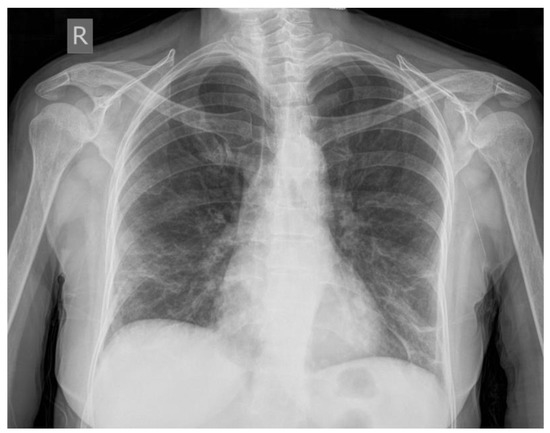

2. Case Presentation

2.3. CT Scan Report